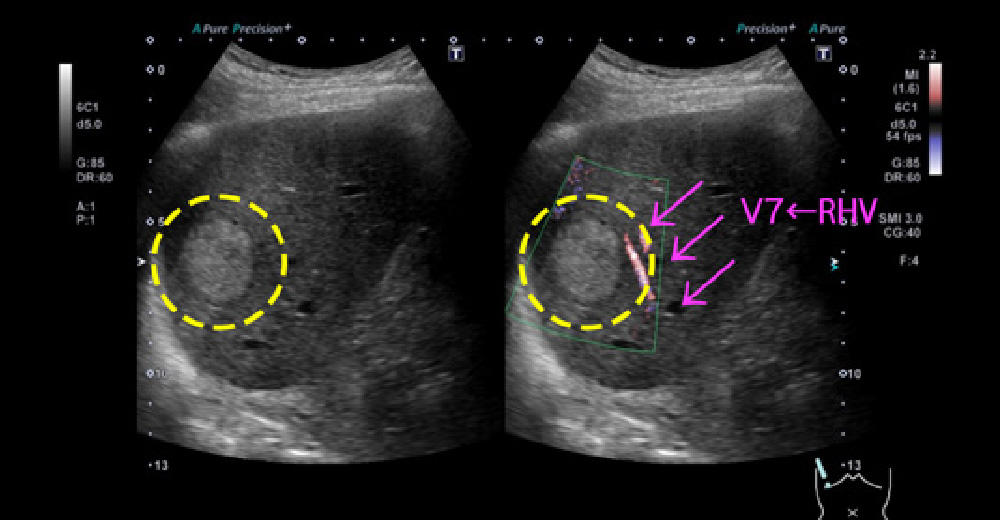

糖尿病併存脂肪肝に、発生した肝がん 糖尿病併存脂肪肝に、発生した肝がん

糖尿病併存脂肪肝に、発生した肝がん